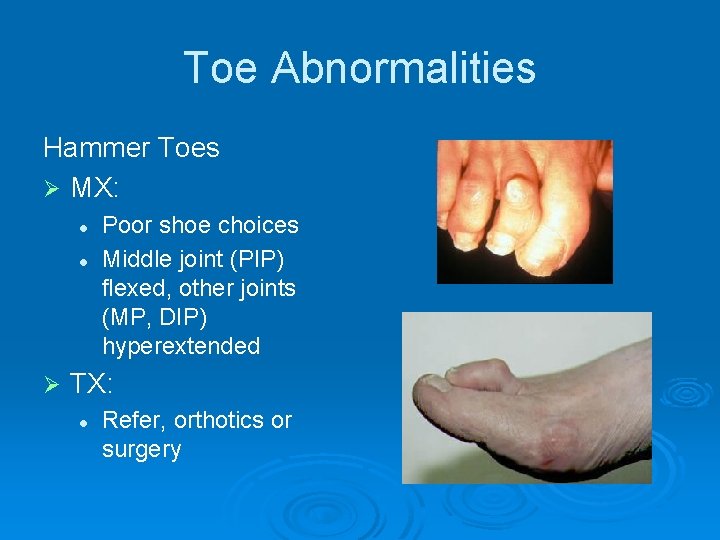

Toe Abnormalities Hammer Toes Ø MX: l l Ø Poor shoe choices Middle joint (PIP) flexed, other joints (MP, DIP) hyperextended TX: l Refer, orthotics or surgery